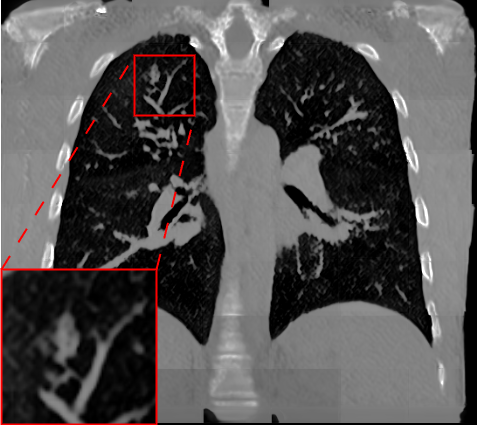

Fig. 2 presents a visual comparison of lung coronal sections from different models. The model using L1 loss results in blurred images, with particularly poor bone reconstruction. In contrast, the MedicalNet-based model produces sharper images but introduces artifacts in anatomical areas. Models based on AFP loss offer visually appealing results, with well-reconstructed anatomical bones and lung tissue. Additionally, only NaviAirway and HAL methods provide detailed bronchial reconstruction, as highlighted in the zoomed-in section.

To handle memory constraints during training and inference, we used a patch-based strategy. We experimented with multiple patch sizes, including and , and also used nnU-Net’s default adaptive windowing strategy (e.g. for thoracic cases). While larger patches provide more contextual information and generally improve reconstruction quality, the overall performance did not differ substantially from nnU-Net’s dynamic patching. Some visible artifacts in Fig.2 result from patch combination, especially in regions not covered by the segmentation network used for AFP supervision. For instance, when the AFP loss relies on the NaviAirway model, artifacts often appear outside the lung fields, as the network lacks anatomical guidance in those regions. However, these artifacts are purely visual and do not affect the downstream segmentation results or the quantitative metrics reported, which are detailed in the upcoming paragraph.

Table 1 presents a quantitative evaluation of the model’s performance on lung MR to CT synthesis, based on the MAE, SSIM, Dice score, and NSD between synthesized and ground truth CT images. The adapted nnU-Net trained with L1 loss delivers the best performance on intensity-based metrics, yielding a MAE of 48.72 and an SSIM of 0.837. In contrast, other models based on perceptual loss or AFP loss achieve average MAE results but maintain competitive SSIM values, for example, the AFP loss with TotalSegmentator embeddings achieves an SSIM of 0.828. In the context of airway segmentations using the NaviAirway pipeline, the adapted nnU-Net models with AFP loss from NaviAirway and HAL’s embeddings deliver the best performance, achieving the highest Dice score of 0.584 and NSD value of 0.723. Conversely, models employing L1, perceptual, or AFP loss with TotalSegmentator’s embeddings yield poorer results, lacking precise bronchial reconstruction. The GAN-based SPADE method generally underperforms compared to nnU-Net, but adding AFP loss to SPADE enhances its performance. These metrics align with qualitative analysis from Fig. 2 and Fig. 3, with the models using AFP loss delivering the best performance in airway reconstruction.